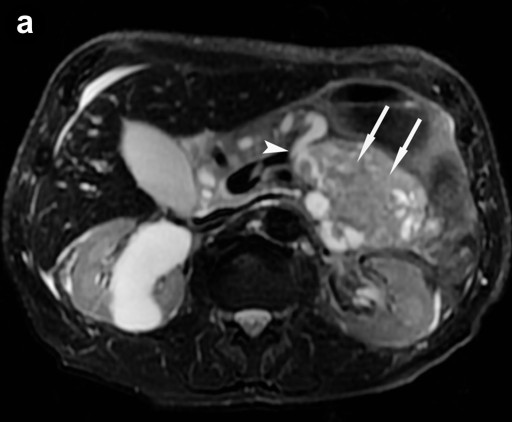

MRI (Signa EchoSpeed EXCITE HD, 1.5 Tesla, GE Healthcare, Waukesha, WI, U.S.A.) was performed and showed two mainly cystic tumors in the pancreatic head and tail with low intensity in T1-weighted images and high intensity in T2-weighted images. The intracystic solid tumor nodules were T1 and T2 hypointense and showed an intensive early, focal gadolinium uptake on dynamic contrast-enhanced T1-weighted images (Figure 2ab). T1-weighted contrast-enhanced images, T2-weighted images, and magnetic resonance cholangiopancreatography (MRCP) clearly depicted the communication between the two separate tumors and the pancreatic duct (Figure 2c).

Figure 2. a. Axial T2-weighted image at the level of the pancreas shows the manifestation of the intraductal oncocytic papillary neoplasm in the pancreatic tail. Communication to the pancreatic duct can be identified (arrowhead) as well as the hypointense solid tumor parts (arrows). b. Axial T1-weighted image after contrast enhancement with gadolinium at the same level also shows communication to the pancreatic duct and strong enhancement of the solid tumor parts (arrows). c. MRCP clearly depicts communication of the dilated pancreatic duct (pd) with the intraductal oncocytic papillary neoplasm in the pancreatic head (asterisk) and tail (arrowhead); the solid tumor components are observable. (bd: dilated common bile duct). |